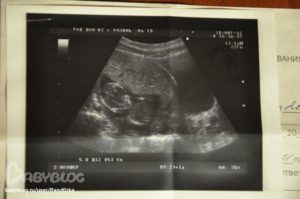

Данное образование нельзя определить при вагинальном осмотре. Хорион – это образование, которое можно увидеть только при ультразвуковом обследовании. Всегда в протоколе УЗИ специалист описывает состояние данной структуры, ее расположение и особенности.

Медицине известно несколько разновидностей верхней оболочки плодного яйца. Стоит отметить, что все они зависят от срока беременности и могут с течением времени сильно изменяться. Определить вид хориона можно только при ультразвуковом исследовании.

Свое название оболочка получила из-за того, что имеет так называемые ворсинки. Именно с их помощью она крепится к внутренней стенке детородного органа. Ворсинчатый хорион всегда описывается в протоколе УЗИ. Также отмечается место его расположения.

Во время ожидания малыша женщины проходят различные исследования. В том числе и УЗИ. При таком обследовании доктор всегда исследует хорион и отмечает его локализацию. При этом учитывается размер оболочки, наличие отслоек и других проблем.

Единственным методом диагностики прикрепления и предлежания хориона является УЗИ! Его проводят на ранних сроках, когда уже можно диагностировать отклонения и предупреждать развитие осложнений.